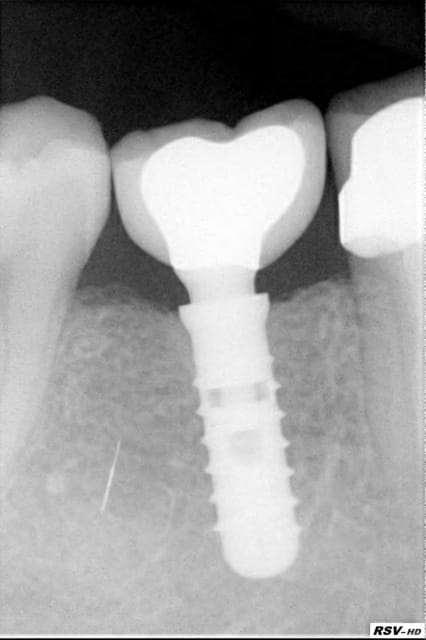

pose d'un axiom en 4*12 en juillet en sous crestal comme il le faut.

et aujourd'hui raido début de cratérisation : petite mais existante;

vu aujourd'hui lors de la mise en place vis de cicat petite operculisation de la vis de couv en palatin (discrète mais existante) donc ouverture nettoyage et mise en place de la vis de cicat .

la forme de cette vis de cicat ne serait elle pas un chouilla agressive pour le TC ? votre avis les poseurs ?

pour la forme et le fond pano avant retro à la pose et rétro aujourd'hui

pour info déja trois cas similaires au maxillaire pas à la mandibule.

et c'est un axiom en 4*12 pas un krestal